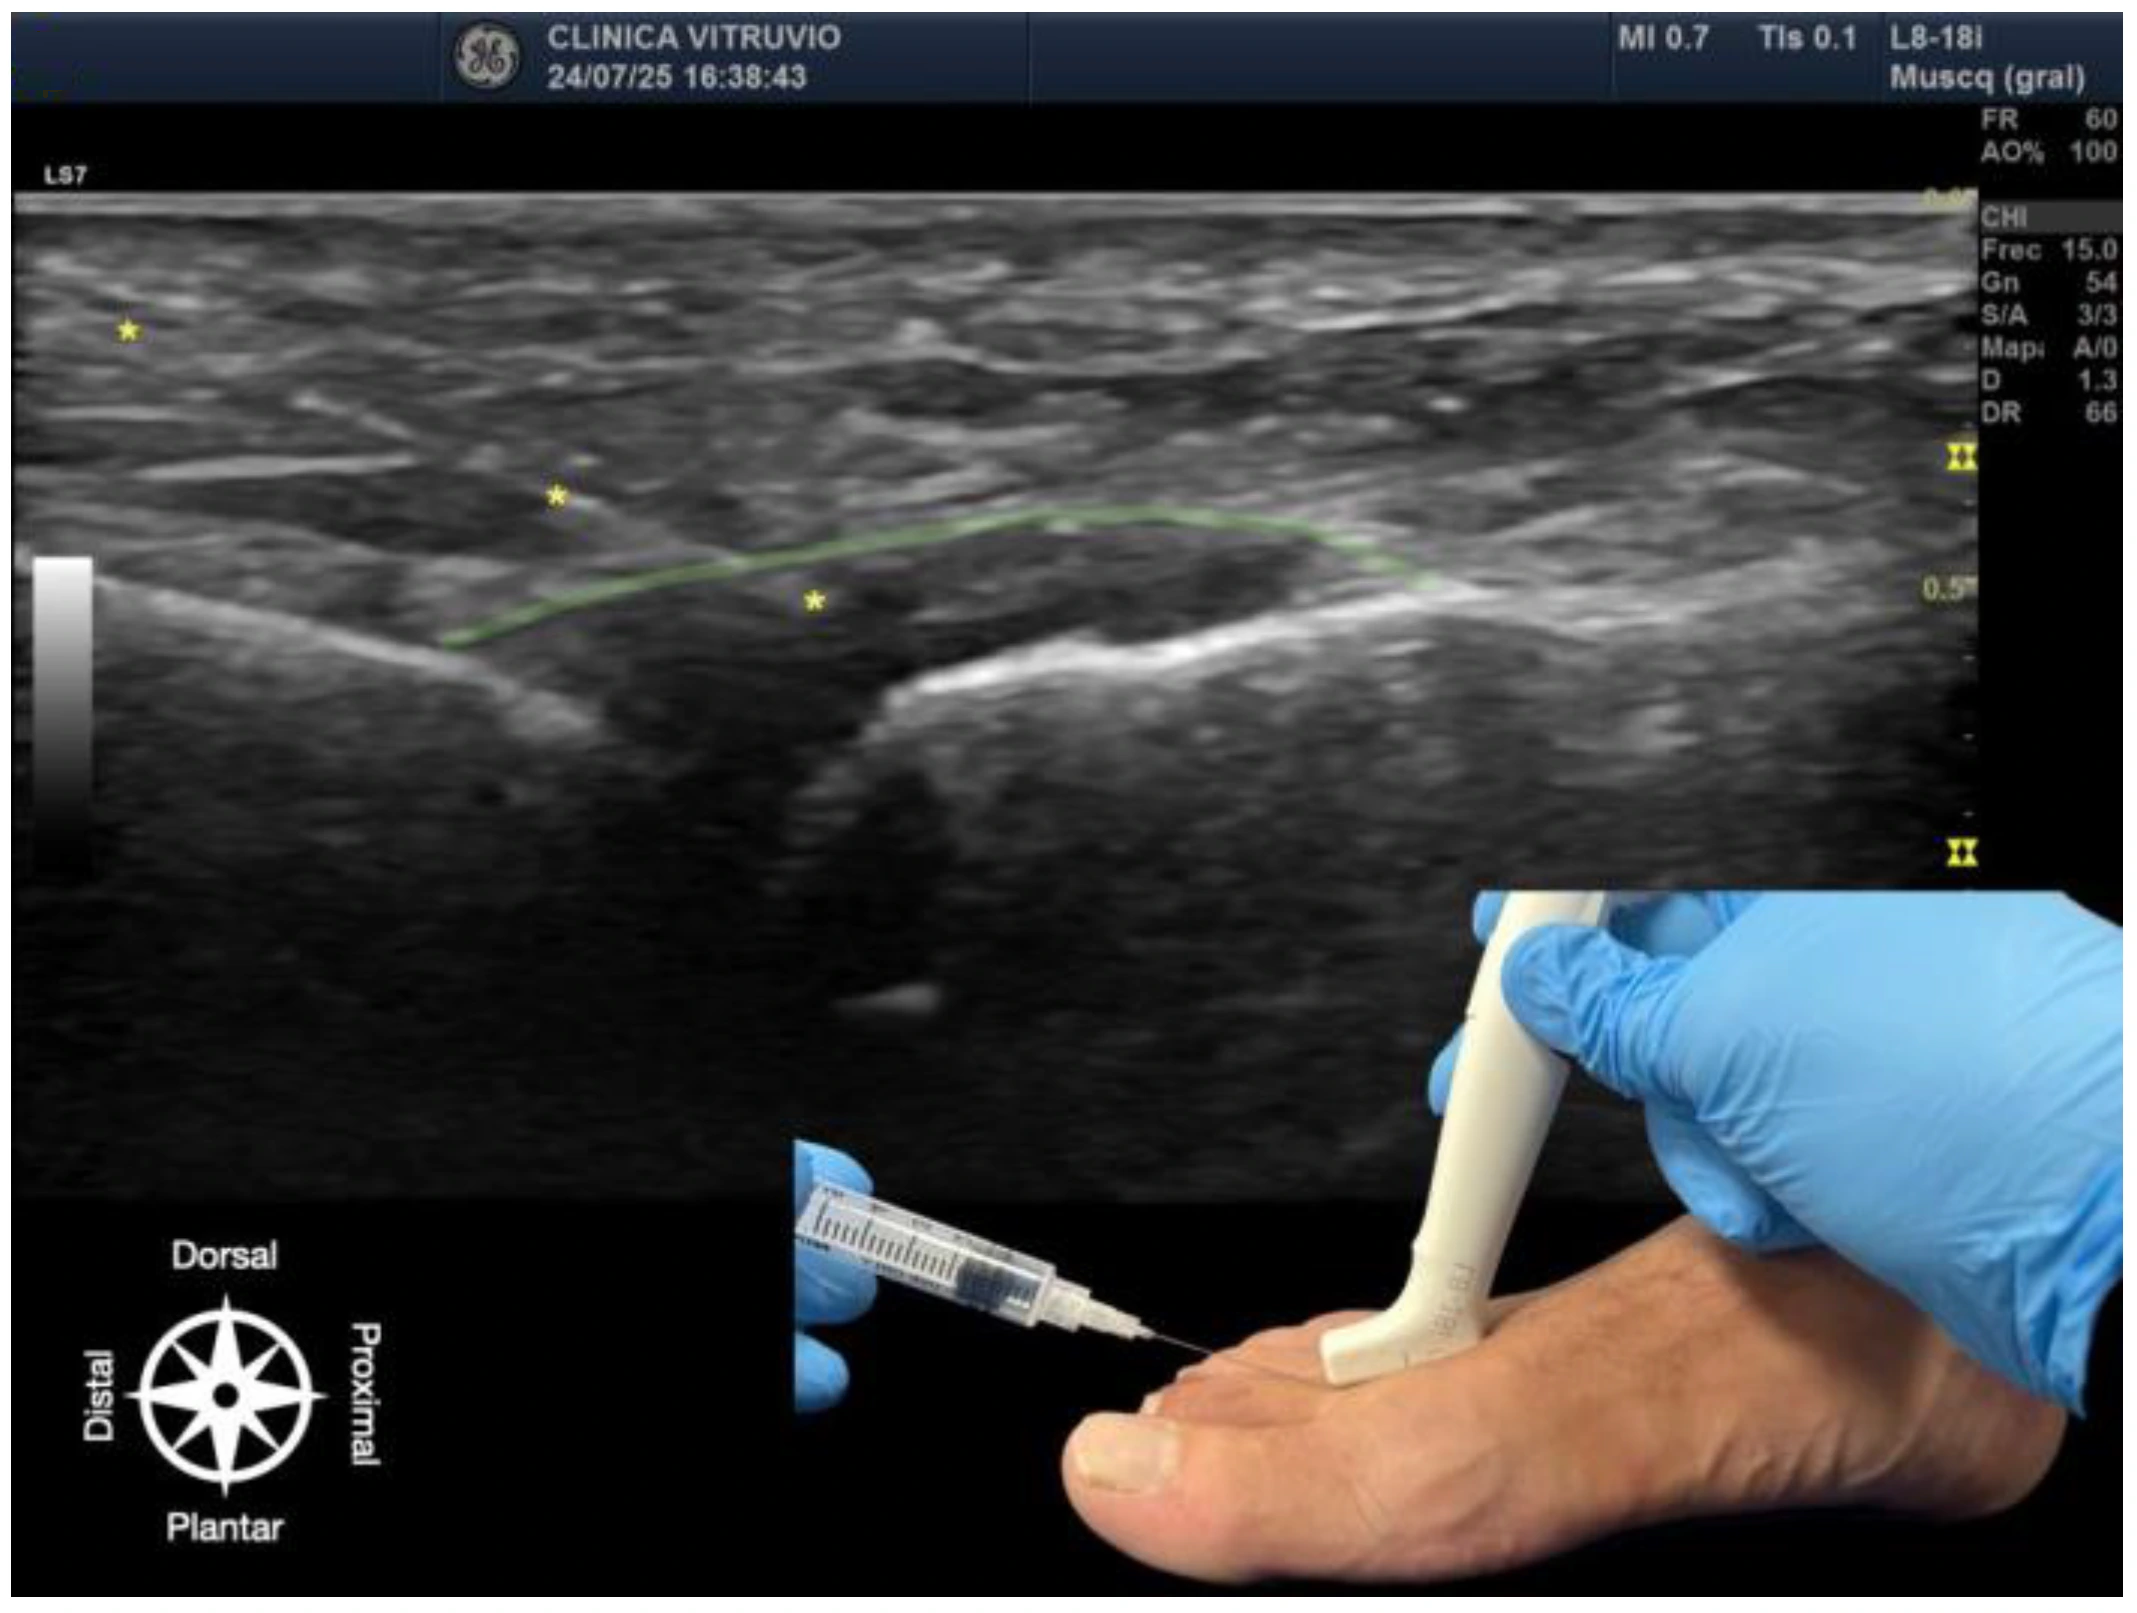

The procedure was performed using high-resolution ultrasound (10–15 MHz linear transducer) under real-time guidance (Figure 1 and Figure 2), following the selective infiltration protocol described by Ruiz Santiago et al. for Morton’s neuroma [3]. Three injections were performed on each anatomical specimen: 1—metatarsophalangeal joint of the third ray (3rd MTP joint), 2—metatarsophalangeal joint of the fourth ray (4th MTP joint), and 3—intermetatarsal space between the third and fourth rays (IM space).

Figure 1. Ultrasound-guided intra-articular infiltration of the metatarsophalangeal joint (Dorsal view). The joint capsule (dorsal recess) is highlighted in green, showing the needle, marked with an asterisk (*) in yellow, inside the articular space. In the lower right corner, the dorsal approach with probe and needle placement is displayed. The anatomical orientation diagram indicates the proximal–distal and dorsal–plantar axes.